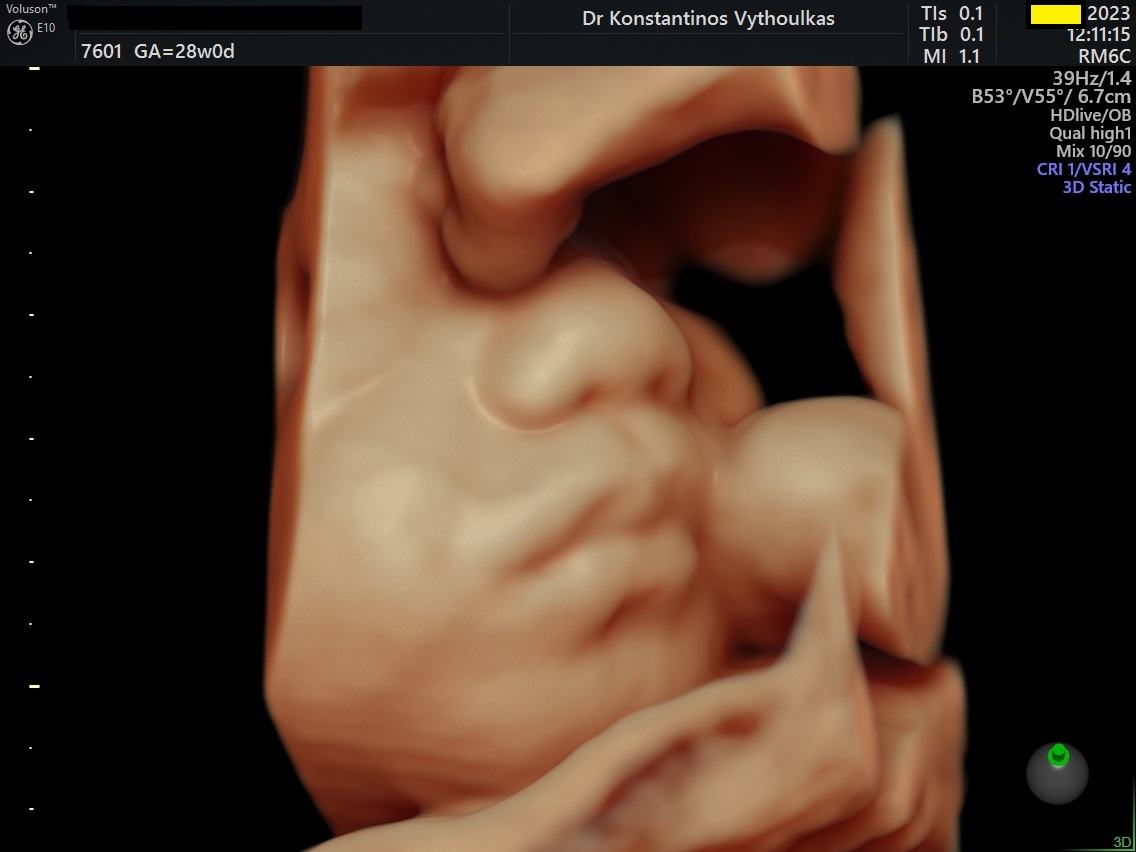

Φωτογραφίες από το αρχείο και από το χώρο του ιατρείου του γυναικολόγου Βυθούλκα Κωνσταντίνου, καθώς και του εργαστηρίου της κυτταρολόγου Λιβέρη Κατερίνας.